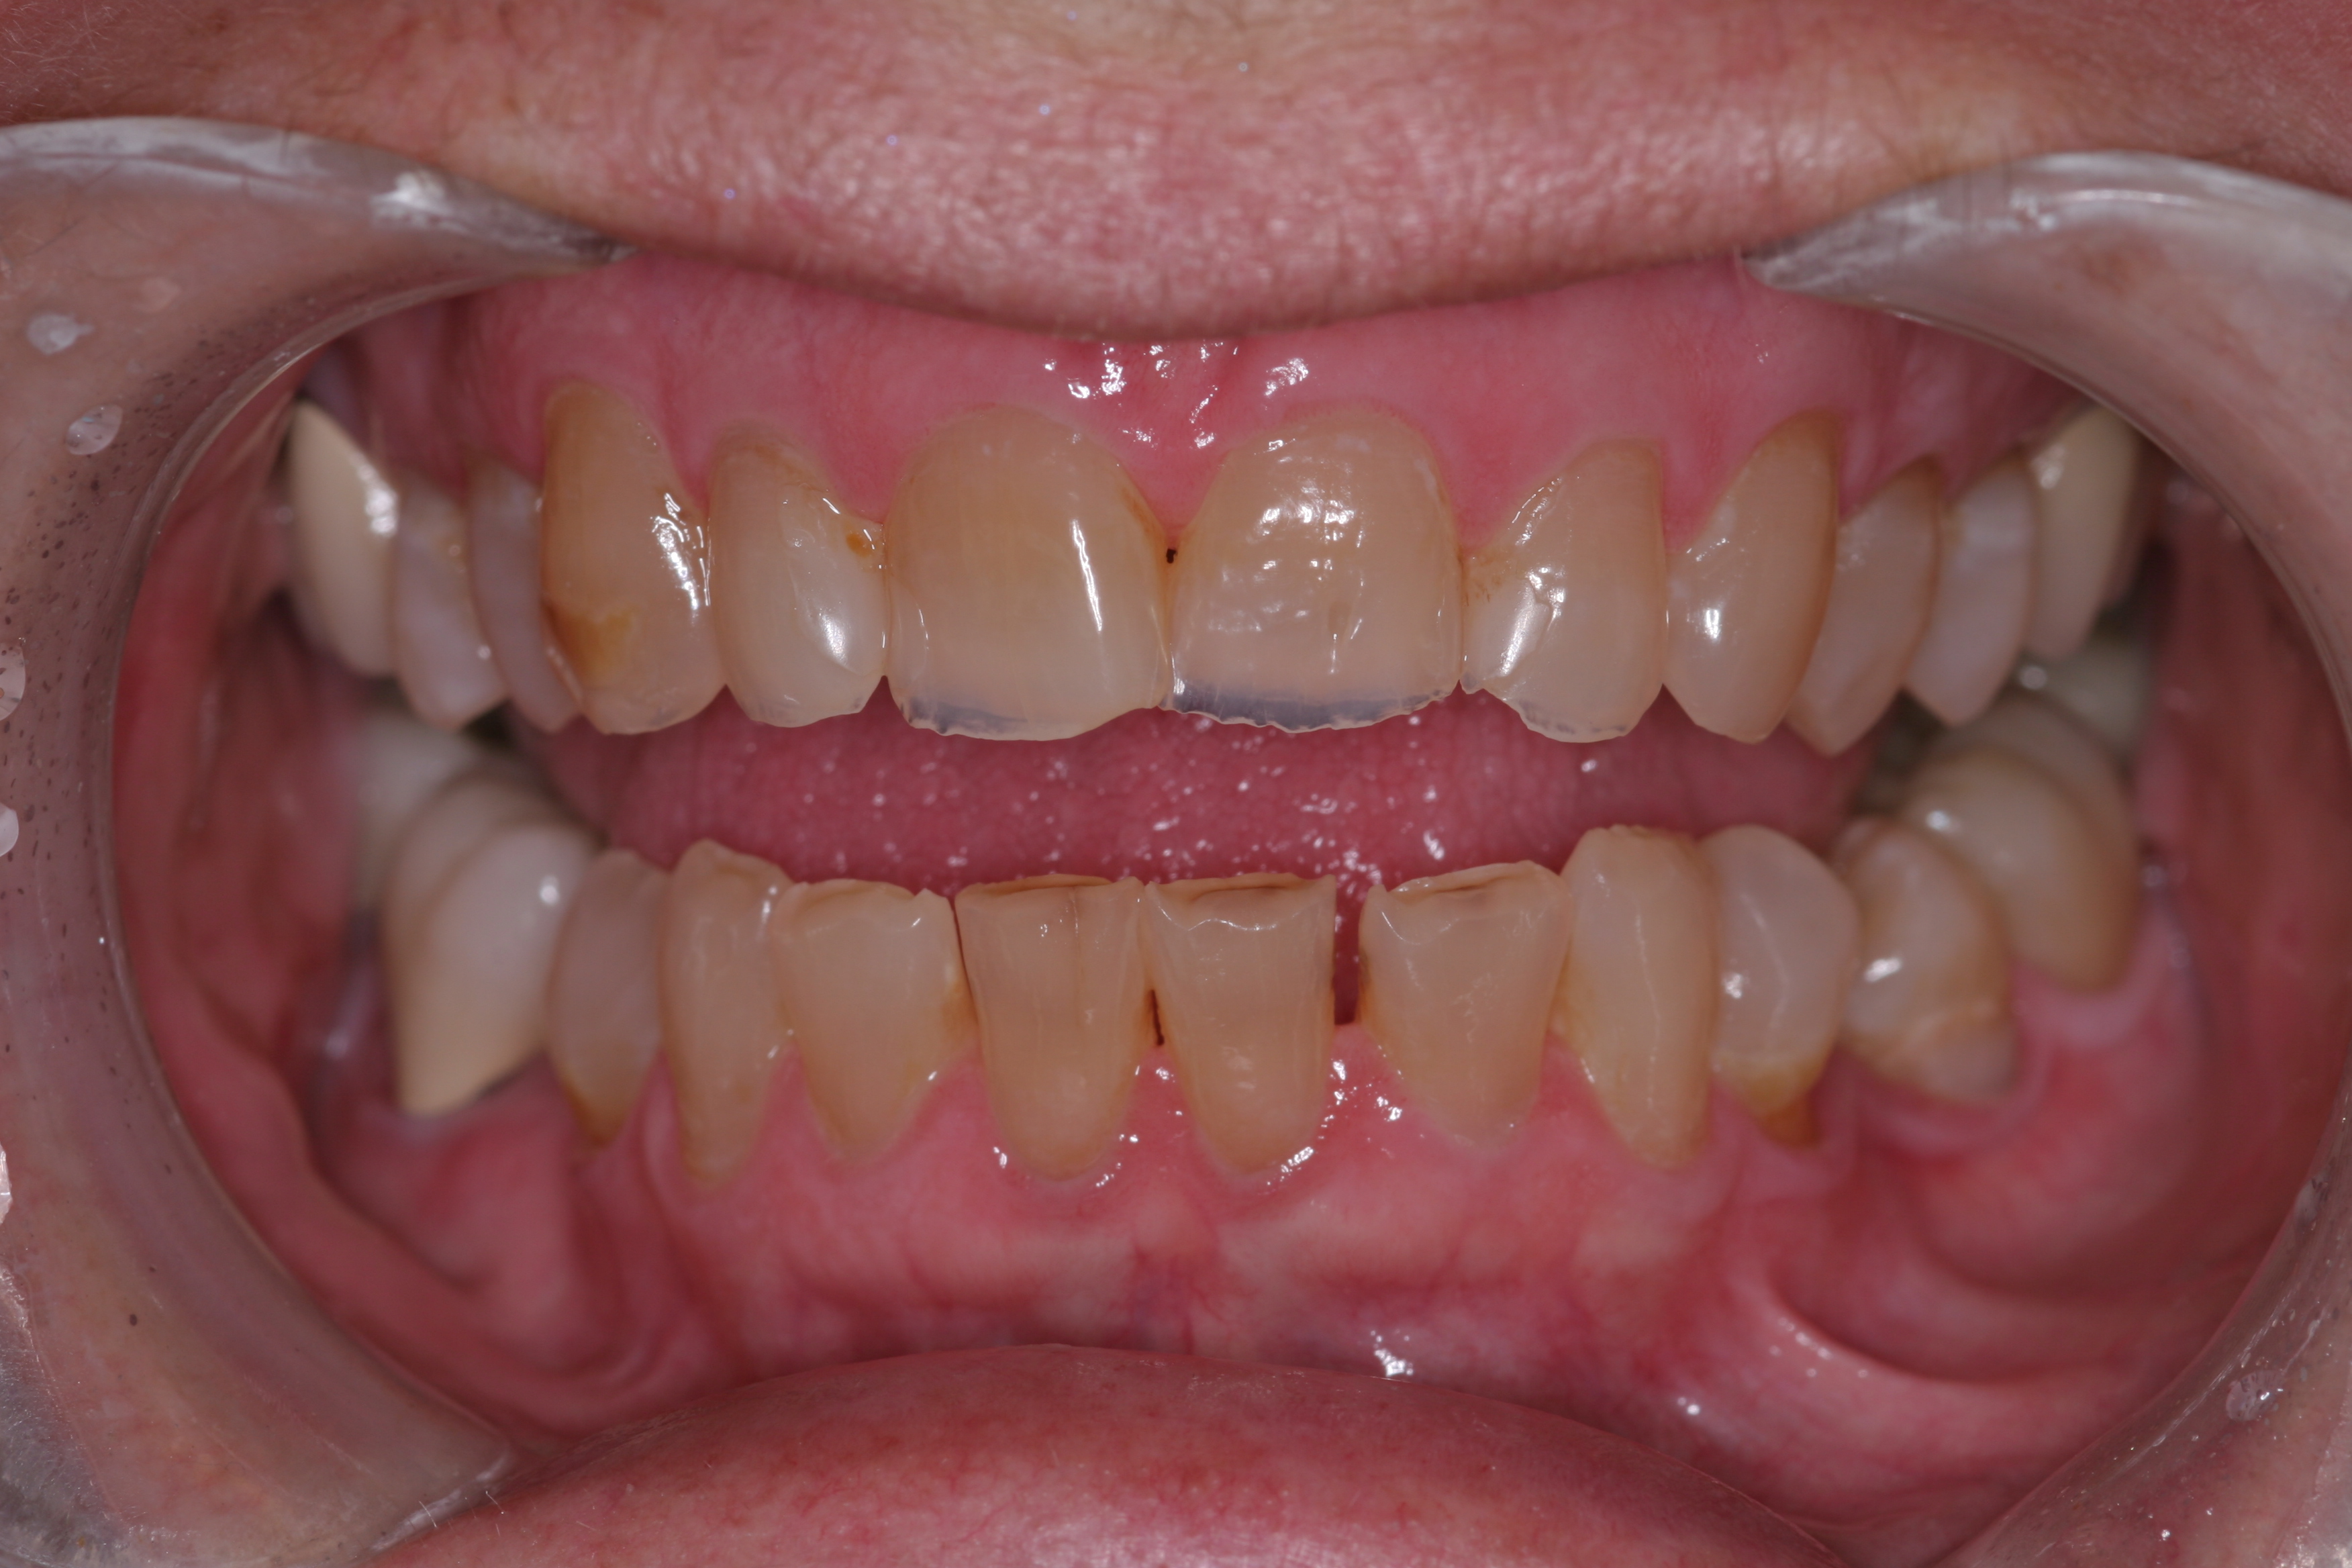

(10.) A patient presented with advanced generalized wear of her anterior teeth, and was displeased with their overall appearance because of their color and wear.

Figure 10

(11.) A patient presented with advanced generalized wear of her anterior teeth, and was displeased with their overall appearance because of their color and wear.

Figure 11

(12.) A patient presented with advanced generalized wear of her anterior teeth, and was displeased with their overall appearance because of their color and wear.

Figure 12